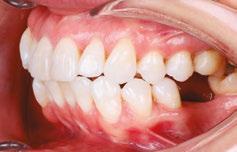

An OMD assessment with TMD muscle pain: a case study

Judith Dember-Paige, BSOHP, COM®, discusses how transformation sometimes takes years, but it’s worth the effort

Stan was referred to my office by a TMD specialist. His chief complaints were he could not chew or open his mouth without pain. It seemed the less he chewed, the more pain he experienced. As a result, an Orofacial Myofunctional Therapy (OMT) program was created to help support his muscles of the TMJ and craniofacial respiratory complex. He used his splint as instructed by his specialist. However, his anterior open bite widened, and his teeth became more misaligned over time.

Upon closer examination, there were contributing factors that led to his discomfort. Stan had been a stomach/face sleeper for years. He also bit his nails since childhood, had a smoking habit from his youth, and he was prone to ear infections. He had moderate tongue and buccal ties, obligate mouth breathing, aggravated by a deviated septum, narrow nares, low tongue resting posture, an anterior open bite, a lower jaw that deviated upon opening, and bouts of acid reflux.

When the tongue rests in the palate, it impacts facial development especially for children who are still growing. An adult, for example, like our friend Stan, the progress made is gradual but more likely to last a lifetime. Generally, therapy starts out once a week for about 2-3 months. Then therapy progresses to every other week for 2-3 months, and then changes to once a month for about 5 months for the rest of the year. The exercises are done a minimum of 2 times everyday. These exercises are designed to strengthen and tone the orofacial muscles, building brand new neuromuscular function. When the muscles of the face are well developed, it may favorably impact appearance and the overall integrity of the facial structures. The muscles of the face also include the tongue, lips, cheeks and neck. Although the therapy program is typically only a year, Stan really liked how good he felt and decided to continue with some of the exercises to this day. From the photos you can see how much the program has impacted his health and well-being.

During his therapy, there was a discussion about the possible benefits he may receive from having his jaws expanded, making more room for his tongue, then to be followed by a tongue and buccal frenums release. His intermolar width is 34 mm, and his intercanine width is 25 mm. I feel any expansion has a potential benefit.

To document any initial assessment, the midpoint of therapy, and when therapy has ended, it is important to take detailed photos, videos, plus full measurements of the face and teeth. This makes it possible to compare results while showing that your therapy works based on the evidence you gathered before, during, and after treatment.

Figure 5

Figure 6: No room for his tongue

Figure 4: 7 years later on April 10, 2024. Anterior open bite closed a bit

Figure 2: Initial assessment on December 15, 2016 (top left). Later September 20, 2017, his anterior openbite widened (top right)

Figure 3: Milled orthotic splint